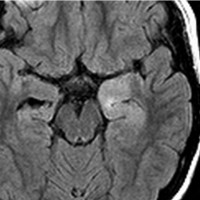

Tourette syndrome(音声と行動のチック,不随意運動)で発症した男児です。石灰化もありのう胞も伴う大脳基底核gangliocytoma grade 1で,摘出にはリスクがあると判断して46グレイ23分割の定位放射線治療をしました。しかし治療抵抗性で増大したために,上側頭溝からの経路で腫瘍を摘出(右の画像)しました。それ以来13年が経ちますが再発はありません。グレード1の神経節細胞腫は放射線治療抵抗性のものが多いと考えた方がいいし,より大きな線量を使用しても同じ結果なのでしょう。